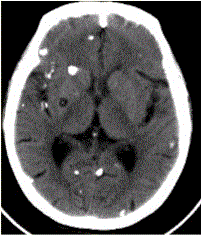

患者男,45岁。头痛、癫痫10余年。查体:无发热,双侧肢体肌力正常。脑电图示双侧额颞叶棘波放电。CT表现如下图。头颅CT检查中,可见囊虫头节钙化,...

问题 患者男,45岁。头痛、癫痫10余年。查体:无发热,双侧肢体肌力正常。脑电图示双侧额颞叶棘波放电。CT表现如下图。 头颅CT检查中,可见囊虫头节钙化,其分期是

选项 A.囊胞期 B.胶样囊胞期 C.肉芽肿结节期 D.结节钙化期 E.脑膜型 F.脑实质型

答案 D